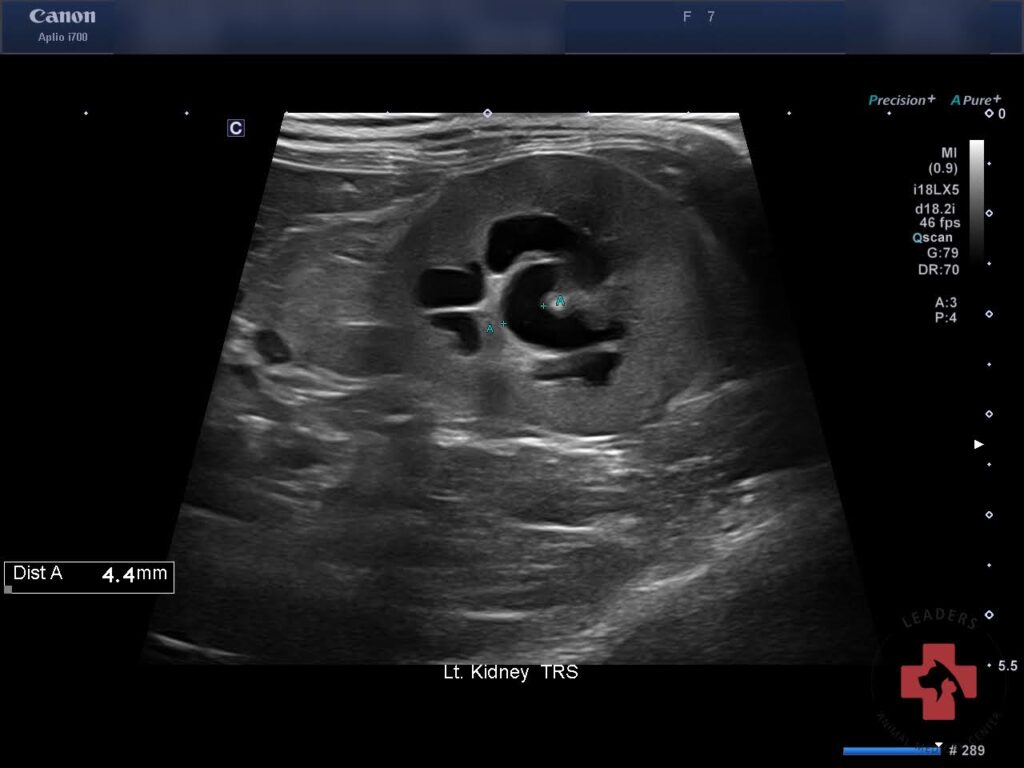

이후 실시한 본원 초음파 검사에서 양측 신장 주위 복막염 신장 피질 비후 양측 신장 신우 확장이 동반된 급성 신부전 변화가 확인되었습니다.

내원 당시 초음파검사(좌측) / 출처: 동탄리더스동물의료원